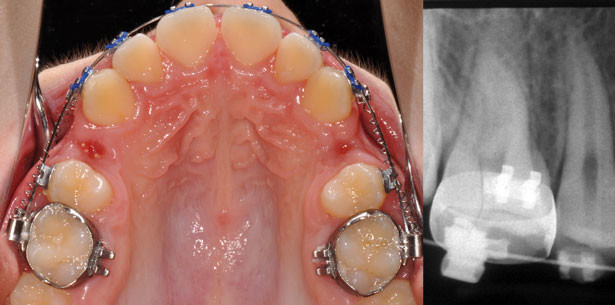

Aus diesem Grund sahen wir einen Bedarf für klinische Studien mit der Frage nach der Möglichkeit einer Zahn- bewegung durch augmentierte Areale gegeben. Das Ziel war die Prognose der Behandlung abzusichern und das Risiko klinischer Misserfolge zu minimieren. NanoBone® (ARTOSS, Deutschland) ist neben bovinem Knochenersatzmaterial und β-TCP wissenschaftlich eines der am besten untersuchten Materialien. Legt man die Anforderungen nach Biokompatibilität, Osteoinduktion, Osteopromotion bzw. Osteokonduktion, Porosität, Stabilität bei Belastung, Resorbierbarkeit bzw. Degradierbarkeit, Plastizität, Sterilität sowie stabile Langzeitintegration von Implantaten (Kolk et al. 2012) für ein „ideales“ Knochenersatzmaterial zugrunde, so sind für dieses Material viele dieser Eigenschaften gegeben (Abshagen et al. 2009, Canullo et al. 2009, Gotz et al. 2008, Punke et al. 2012, Rumpel et al. 2006). Aus diesem Grund entschieden wir uns für dieses Material in unseren Untersuchungen. In einer Pilotphase wurde die Bewegung durch das Material evaluiert (Reichert et al. 2013, Reichert et al. 2011). Anschließend wurde in einer systematischen Untersuchung zehn Patienten mit kieferorthopädischer Indikationsstellung zur symmetrischen Entfernung von 28 Prämolaren eingeschlossen (Reichert et al. accepted). Im Split-mouth-Design wurde eine Seite mit NanoBone® behandelt, die Gegenseite diente als Kontrolle. Nach der primären Wundheilung wurde der Lückenschluss mit einer standardisierten Mechanik vollzogen (Abb. 1a–e). Neben einer Röntgenkontrolle wurde zum Zeitpunkt des Lückenschlusses das Vorhandensein von Gingivaduplikaturen, eine durch eine Atrophie bedingte Einfaltung der Schleimhaut nach dem Lückenschluss (Golz et al. 2011), sowie die Sondierungstiefen begrenzend zur Extraktionsregion dokumentiert. In dieser Studie konnte der Lückenschluss in allen Fällen durchgeführt werden und alle Zähne blieben vital. Man konnte darstellen, dass die Augmentation mit dem erwähnten Material den Ausprägungsgrad entstandener Gingivaduplikaturen sowie die Sondierungstiefen mesial und distal der Extraktionsregion gegenüber der Kontrollseite signifikant verringerte. 70 % der Röntgenaufnahmen zeigten transluzente und röntgendichte Areale in der Augmentationsregion (Abb. 2a und b) und apikale Wurzelresorptionen wurden seitengleich bei nur zwei Patienten festgestellt. Somit lässt sich schlussfolgern, dass eine Zahnbewegung durch das verwendete Knochenersatzmaterial prinzipiell möglich ist. Bezüglich der röntgendichten Areale bleibt jedoch eine kleine Restunsicherheit, daher stehen Langzeituntersuchungen aus, um mögliche Nebenwirkungen letztlich ausschließen zu können.